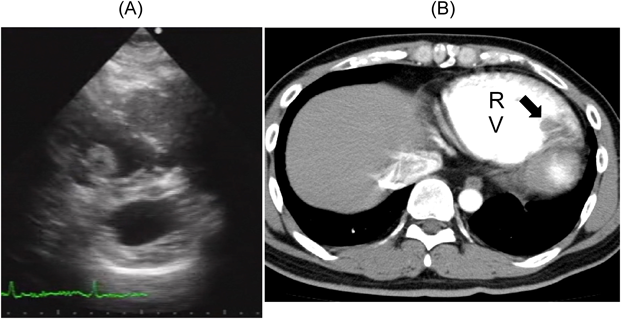

ダビガトランで右室内血栓が消失した不整脈原性右室心筋症の1例Dissolution of a Right Ventricular Thrombus with Dabigatran Etexilate in Arrhythmogenic Right Ventricular Cardiomyopathy